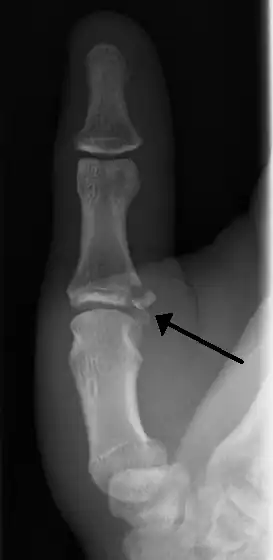

Avulsion fractures of the ulnar base of the proximal phalanx of the thumb ( Gamekeeper's fracture )

When approaching this type of injury, the physician must first determine whether there is an incomplete rupture (or sprain) of the UCL, or a complete rupture. If the UCL is completely disrupted, the physician must then determine whether there is interposition of the adductor aponeurosis (Stener lesion), or simply a complete rupture of the UCL with anatomic or near-anatomic position. Radiographs are helpful in determining the possible presence of an avulsion fracture of the proximal phalanx insertion site of the ulnar collateral ligament. Stress examination, or one done under fluoroscopic guidance, can help determine the integrity of the ligament.